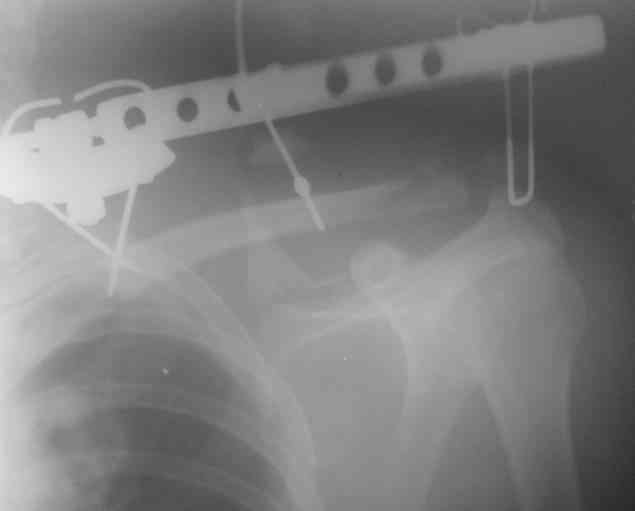

Планирую через четыре недели сделать рентген-контроль с решением вопроса об удалении АВФ. Аппарат смонтирован из деталей аппарата Илизарова. Картинки в приложении.

К сожалению оригинального аппарата Сушко нет в наличии (даже в глаза не видел), но использовался сам принцип метода по Сушко-Илизарову. Цитирую из "Основ по чрезкостному остеосинтезу аппаратом Г.И. Илизарова" (Л.Н.Соломин, 2005): 1. В каждый костный фрагмент должно быть введено не менее двух 2-мм консольных спиц, расположенных под углом к друг другу. 2. Места введения спиц должны располагаться вблизи суставных концов ключицы.

3. Точки введения спиц должны находиться на верхней поверхности ключицы.

4. Плоскость расположения спиц должна совпадать с продольной осью костных фрагментов.

5. При диафизарных переломах спицы проводят через оба кортикальных слоя.

6. При переломо-вывихах акромиального конца ключицы консольные спицы в акромиальный конец ключицы вводят только до упора в противолежащий

кортикальный слой; в акромиальный отросток лопатки консольные спицы не вводят, а используют спицу Киршнера "acr.,6-12", концы которой П-образно загибают навстречу друг другу.

7. Расстояние между поверхностью кожи и внешними опорами должно быть минимальным - в пределах 1,5-2 см.

Посмотрел пациента под рентгеноскопом, определяется изолированный перелом верхнего медиального угла лопатки. Вопрос об операции отпал. Больной машет крылом как пропеллером, пришлось ограничить активность дисциплинирующей "косынкой" ... :))) Отек мягких тканей в области

лопатки купировались через 24 часа после операции. Не смотря на громоздкость конструкции аппара т переносится самим больным легко. Под спортивной курткой не так и заметно. Разрешил мытье под душем с последующей заменой прижимных спиртовых шариков, обработкой АВФ и спиц спиртом 1 раз в неделю. Больной пробыл в отделении 3 койко-дня с дальнейшим долечиванием амбулаторно.